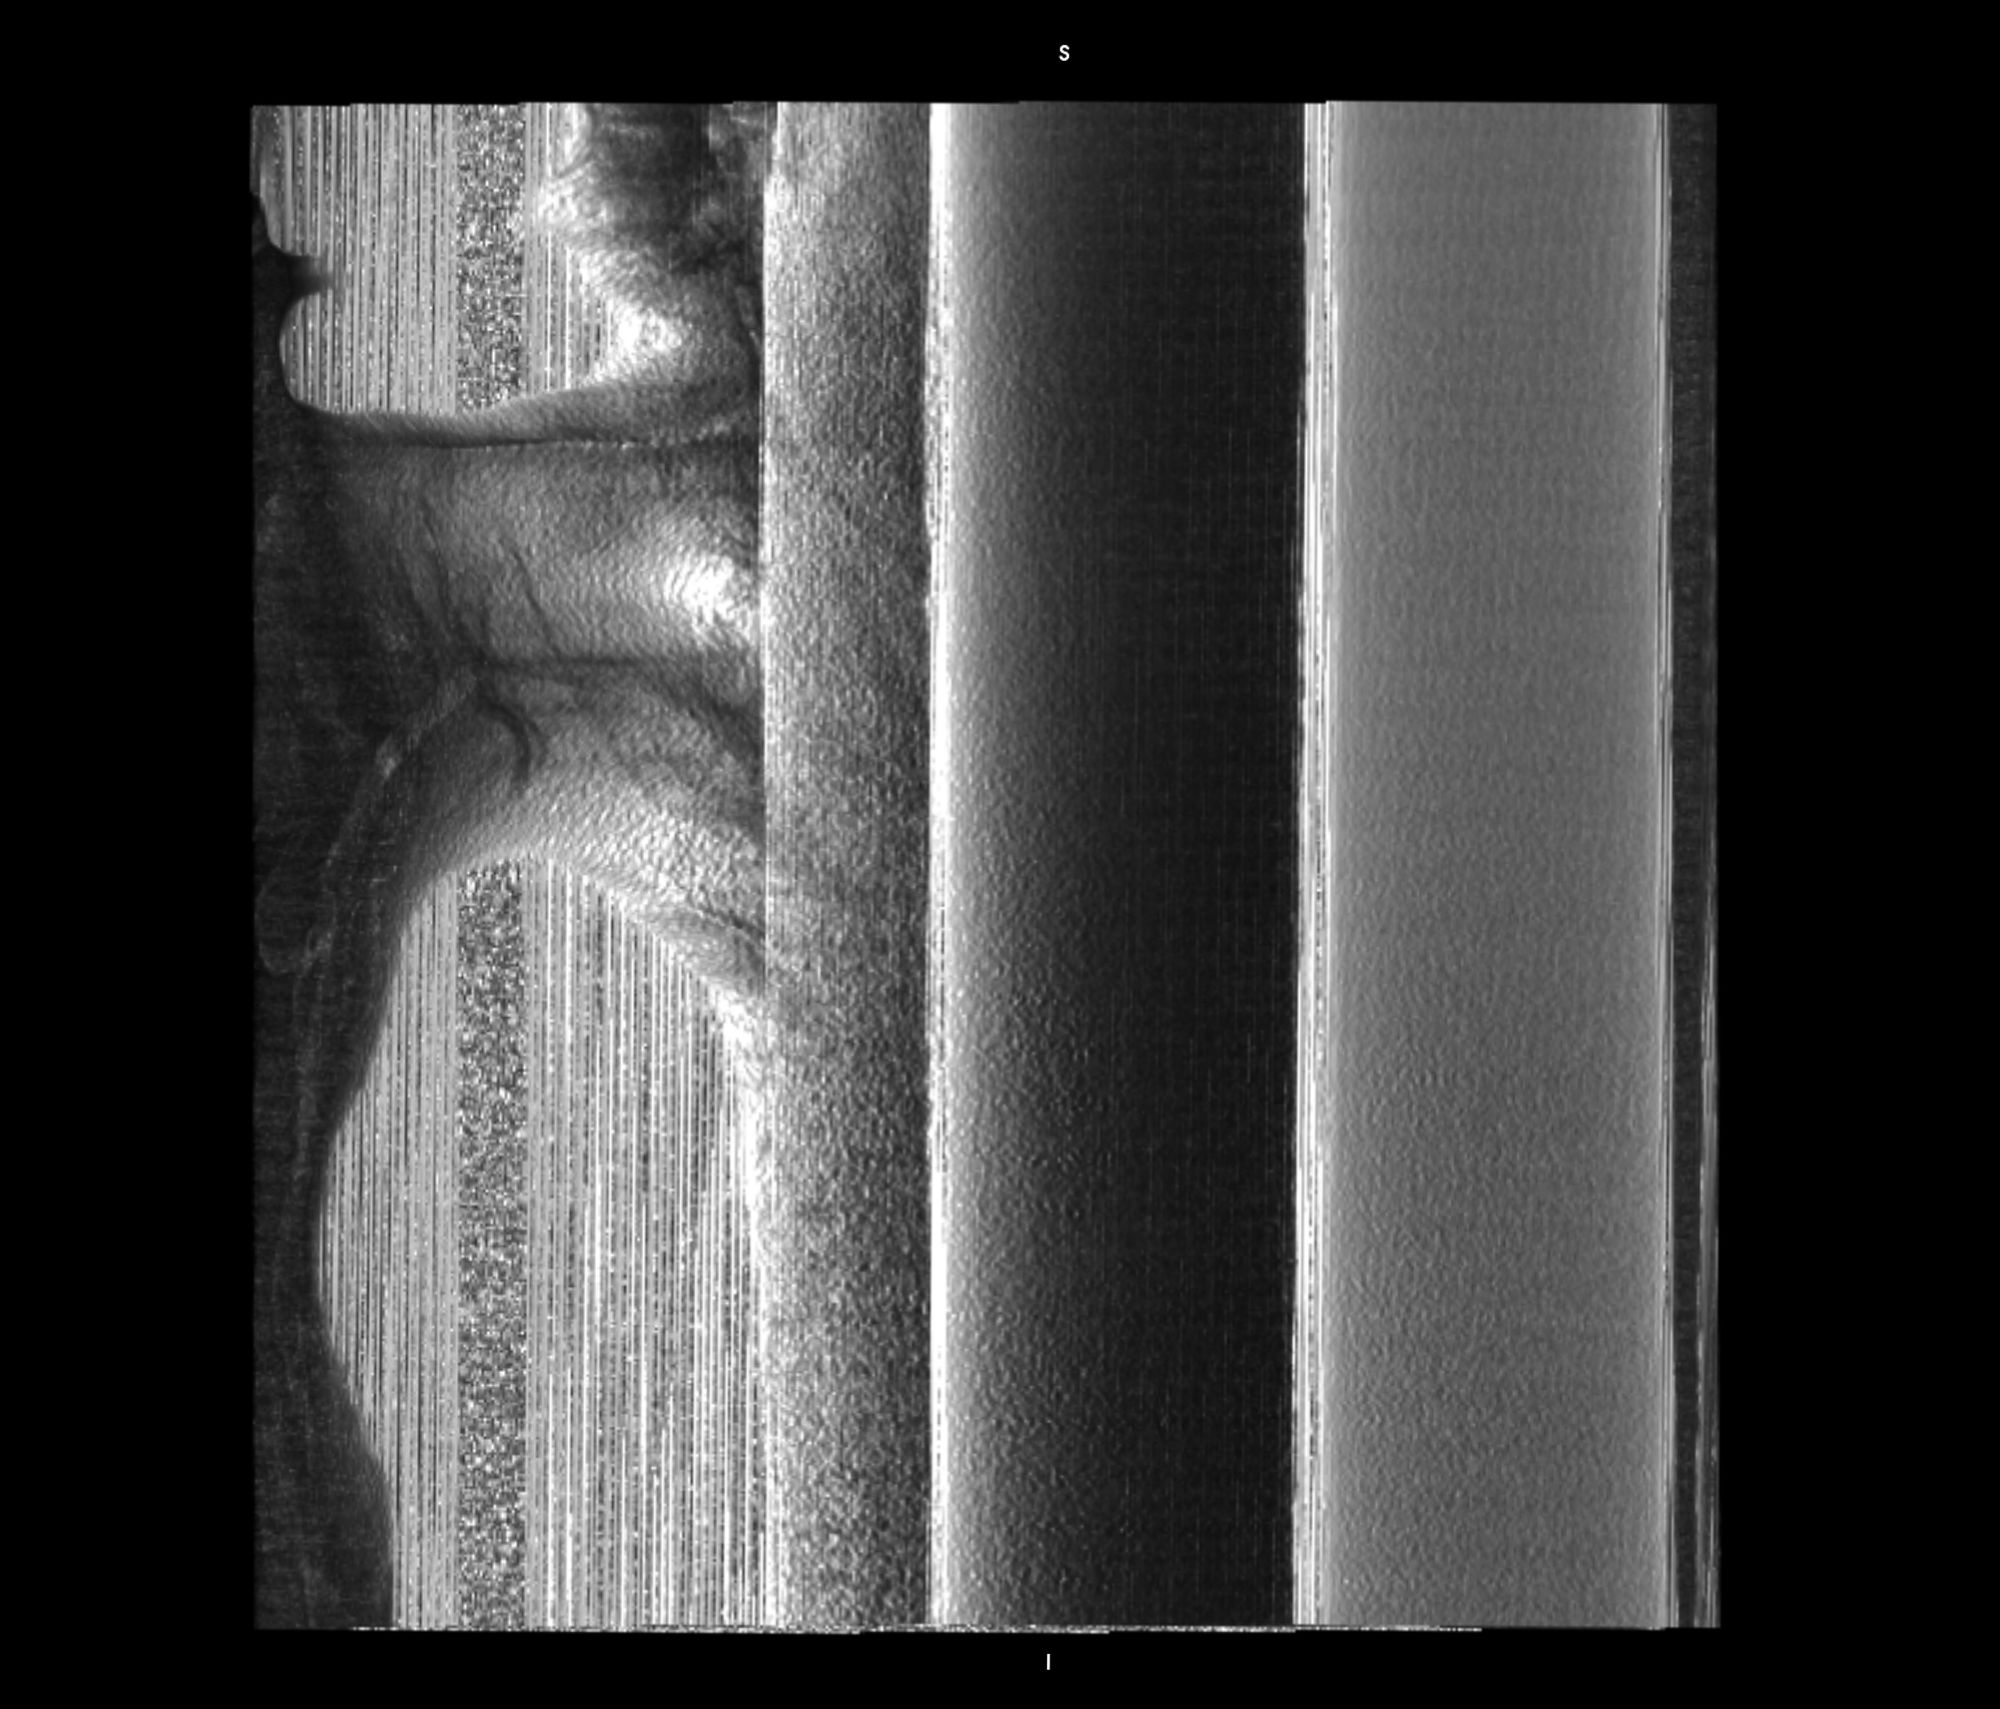

Chasing Intensities considers the body through its relationship to contemporary medical imaging technologies.

In this project, I look at the visual limit between the inside and the outside, the inner and the outer. I combine different visual approaches to materialise the body, using medical imagery, photography from manuals and radiology software. Decontextualised from their origin, these images speak of medicine’s relationship to both sex and violence, and remind us that, in medicine, to go into the body is always to go into the image first.